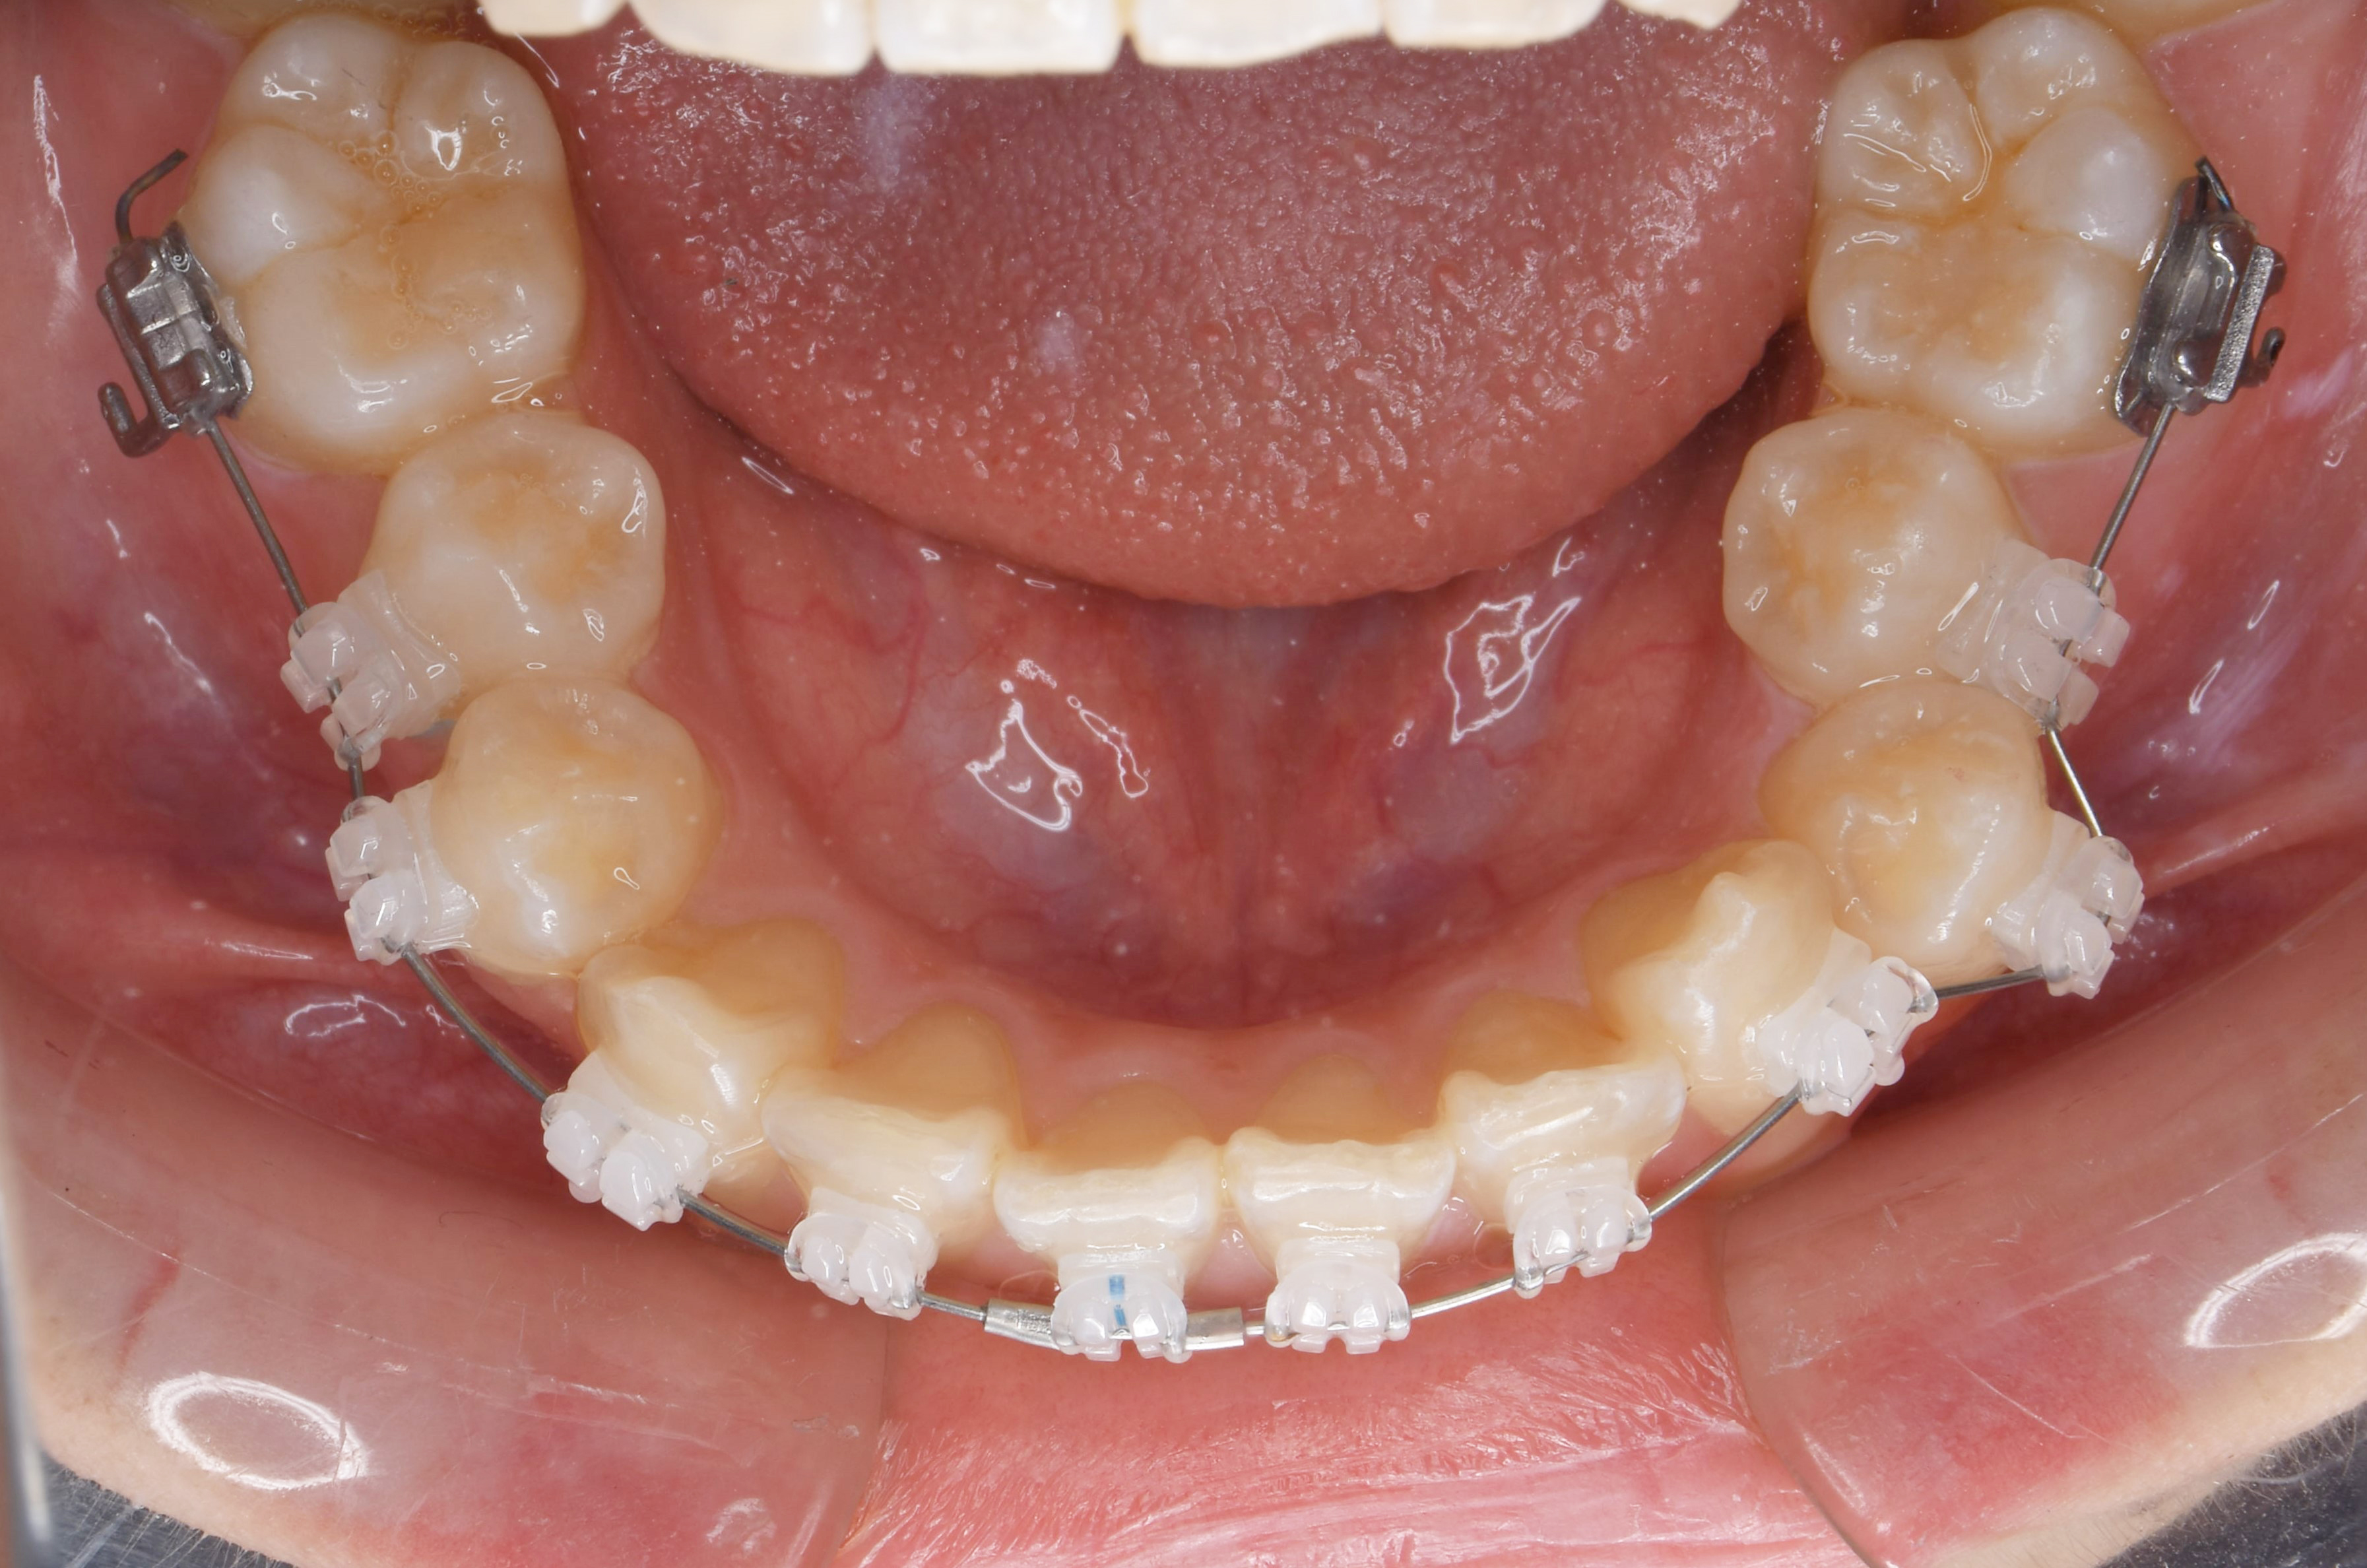

治療前。上顎の前歯の突出の改善を主訴に来院。上顎前歯の前方への突出が著しい。また下顎の前歯が上顎の歯茎を噛んでおり、過蓋咬合(ディープバイト)を呈している。上顎前歯の後方移動と過蓋咬合の改善が必要な症例。臼歯部の上下の咬合関係は完全な2級咬合(下顎遠心咬合)であるため、上顎の左右の第一小臼歯だけを抜歯する計画とした。

矯正治療後。上顎の小臼歯を抜歯したスペースを利用することで、上顎前歯が内側にきれいに並んでいることが分かる。過蓋咬合も改善し、個性正常咬合を確立した。上下の歯の数が異なる変則抜歯のケースでは、抜歯本数を最少に出来るものの、下顎第二大臼歯(一番奥の歯)は噛み合わせにあまり参加できない欠点もある。治療計画は、総合的に最善な結果が得られるよう立案し提案することが重要。